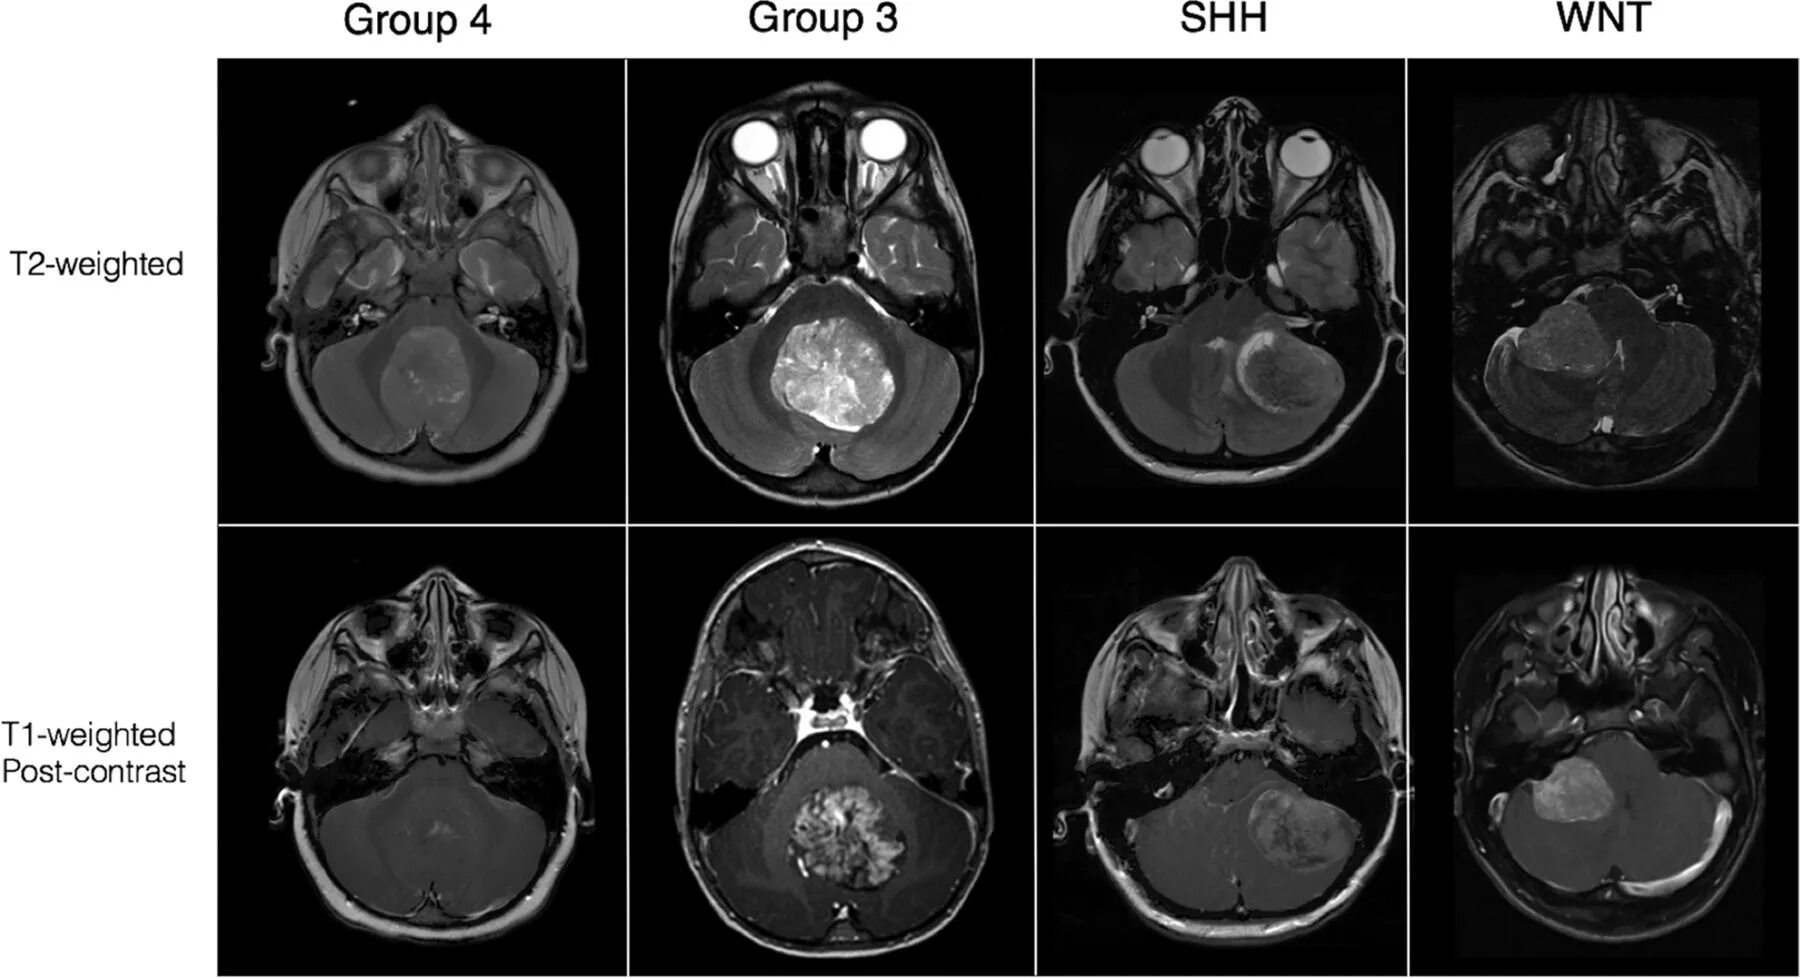

Медуллобластома это